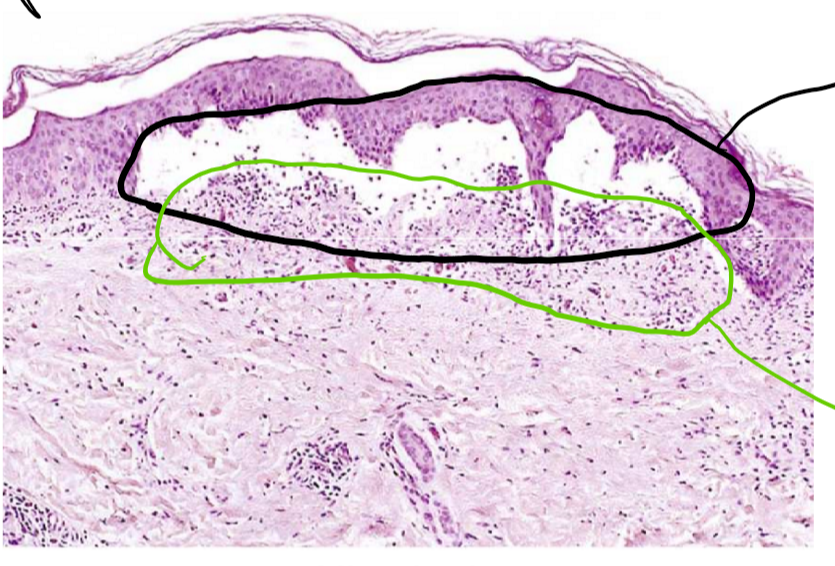

10

Q

c’est quel type de patron morphologique de l’inflammation aiguee?

A

séreuse

en haute c’était des sérosités

en bas un peu inf aiguee